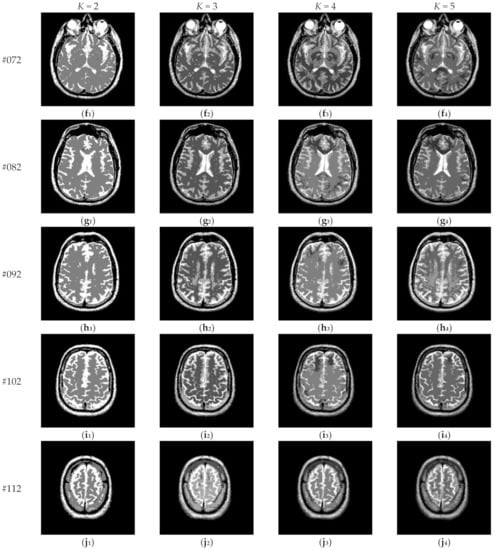

Figure 17 depicts the segmentation results of Proposed for brain slices #022~#112 with the number of thresholds K from 2 to 5. It can be seen that segmentation results with different threshold numbers have different effects. In general, the higher the level of thresholding, the better segmentation quality. Table 4 displays the comparison of optimal threshold values obtained by different algorithms with K = 2, 3, 4, 5. The proposed algorithm and LLF-DCE are based on the fusion scheme. The former combines two different segmentation results obtained by IIMT and HL-IIMT; the latter combines two different segmentation results obtained by LLF-Otsu and DCE-Otsu. In Table 4, it can be seen that the final thresholds selected by different algorithms are different from each other.

Figure 17.

Segmentation results obtained by the proposed algorithm for brain slices #022~#112: (a1–j1) display the results of 2-thresholding; (a2–j2) display the results of 3-thresholding; (a3–j3) display the results of 4-thresholding; (a4–j4) display the results of 5-thresholding.